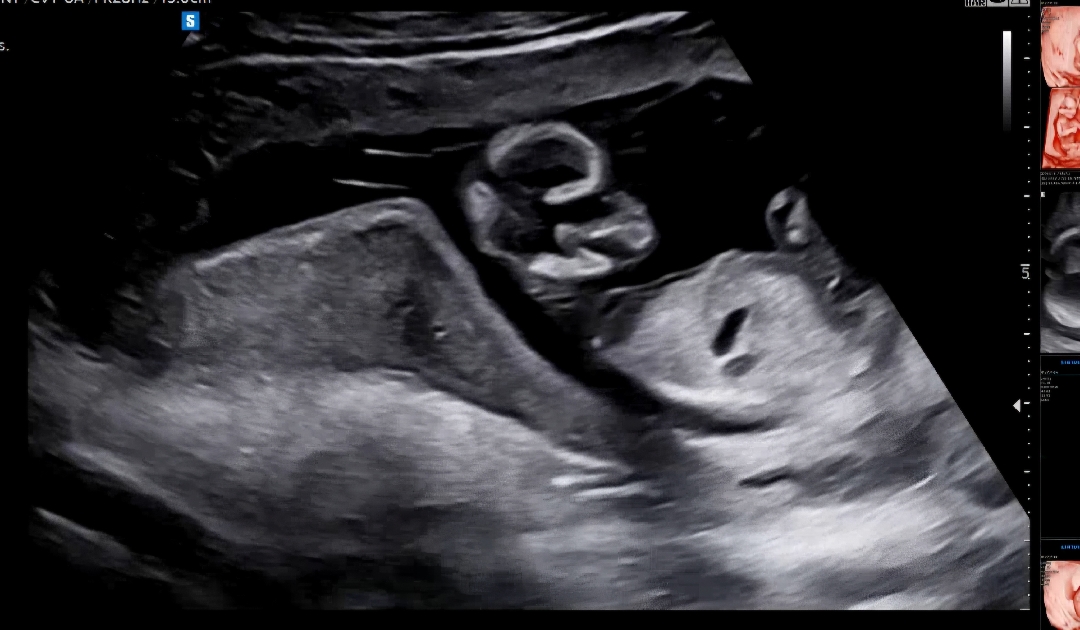

각도법봐주세용

성별 알 수 있을까용??

이시기엔 못봐요~ 너무 이르네요ㅠㅠ

13준데 이른가봐용ㅠㅠ

댓글 사진은 9주라고 되어있어서요! ㅠㅠ 본문 사진은 잘 안보이는거 같아요 ㅠㅠ 아래부분 잘 나온 각도법 사진 있으면 좋을것 같아요❤️

사진이 두장은 안올라가서! 이 사진도 있어요!